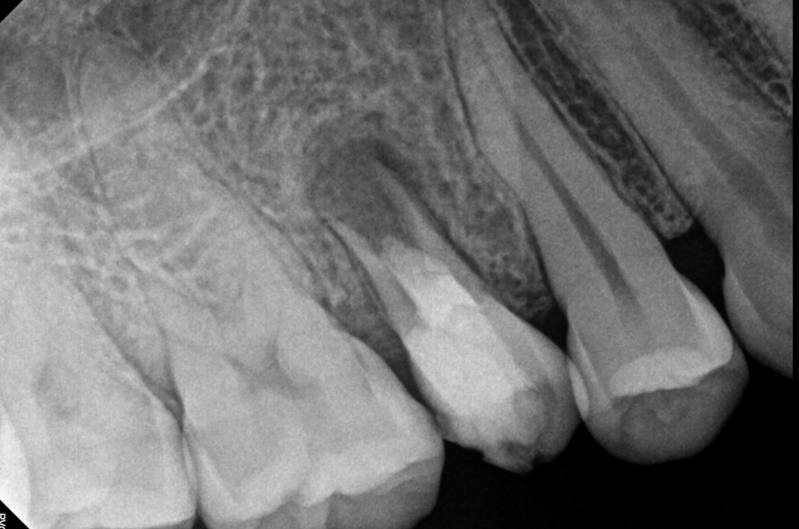

Case: RCT on Tooth #29

19-year-old male with no significant medical history. NKDA.

Meds: None

Dx: Necrotic pulp with chronic apical periodontitis (#29); external root resorption noted

Tx: Root canal therapy

Reflection

Tooth #21 also has had the cervical external root resorption. This case emphasized the importance of early detection in managing external root resorption. While #29 required RCT due to pulpal necrosis, #21 was identified early and successfully treated with a restoration, preserving vitality.